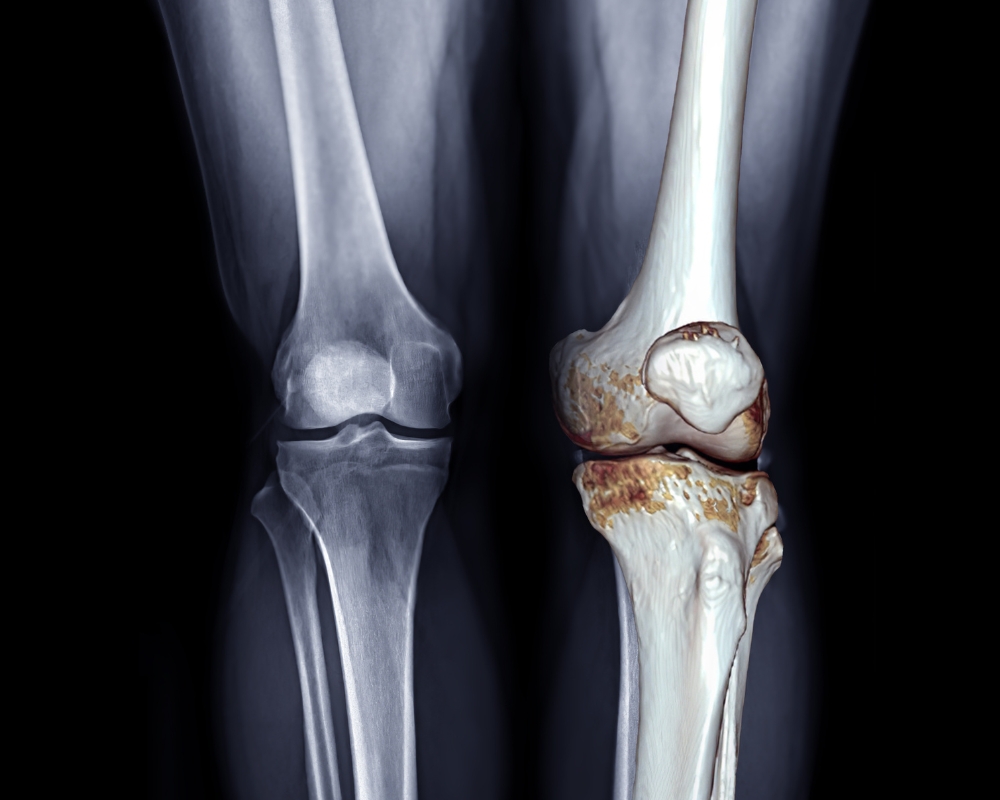

Chẩn đoán hình ảnh phát hiện chính xác thoái hóa khớp gối

- X-quang khớp: Là công cụ phổ biến nhất, giúp phát hiện hẹp khe khớp (do mất sụn), hình thành gai xương, xơ xương dưới sụn hoặc biến dạng khớp.

- MRI (Cộng hưởng từ): Được sử dụng khi cần đánh giá chi tiết hơn về sụn, dây chằng hoặc tổn thương mô mềm quanh khớp.